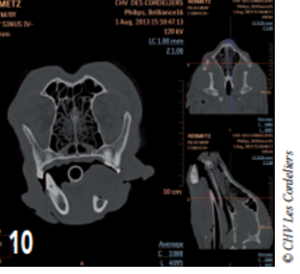

L’ostectomie allait en profondeur jusqu’au canal mandibulaire (photos 9 à 12).

Photo 10 : Coupe transverse de l’image tomodensitométrique postopératoire montrant le canal mandibulaire ouvert.

Photo 11 : Coupe sagittale de l’image tomodensitométrique postopératoire montrant l’étendue de l’ostectomie.

L’ostectomie n’ayant pas créé de discontinuité entre la partie articulaire de la mandibule et la symphyse, il n’y a aucune malocclusion.